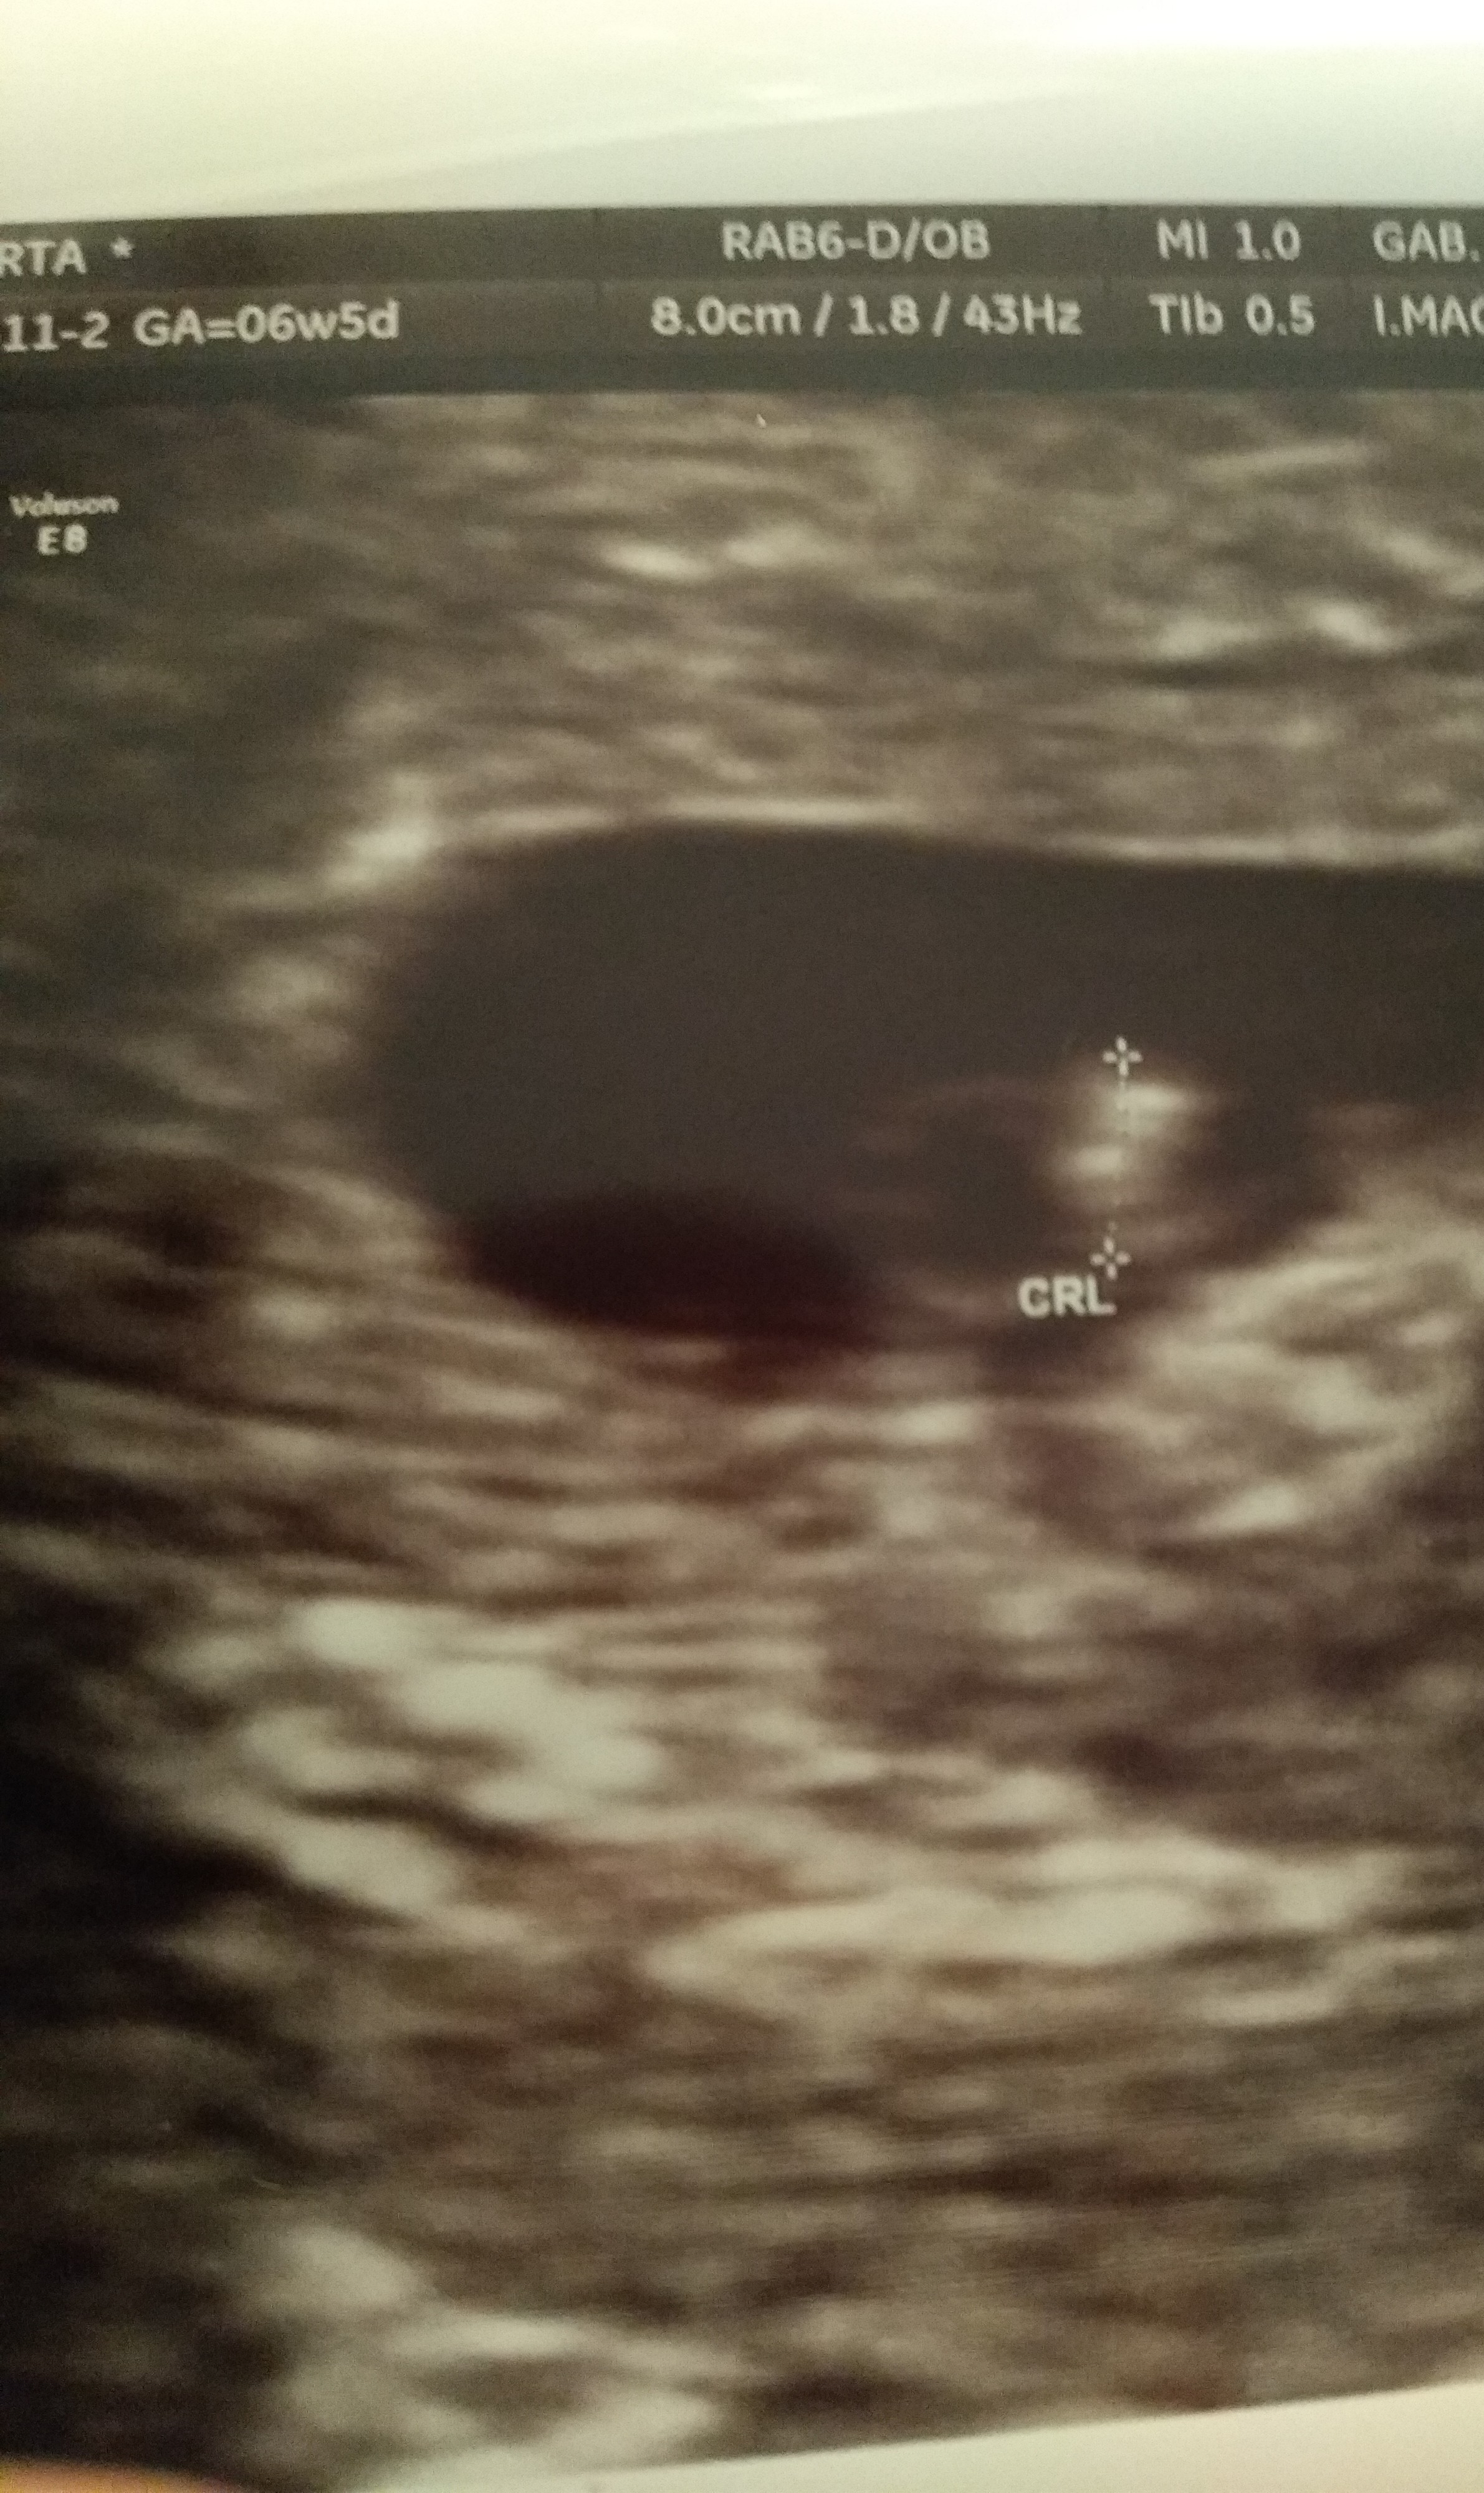

A to moja mała kropeczka. Serduszko biło. Dostałam skierowanie na prenatalne. Biorę luteinę i polocard 150. Do tego kwas foliowy svanson 800. Byłam u dwóch różnych lekarzy i nie wiem na kogo się zdecydować aby prowadził mi ciążę.

• IMG_20190909_195732~2.jpg

1,7 MB · Wyświetleń: 139